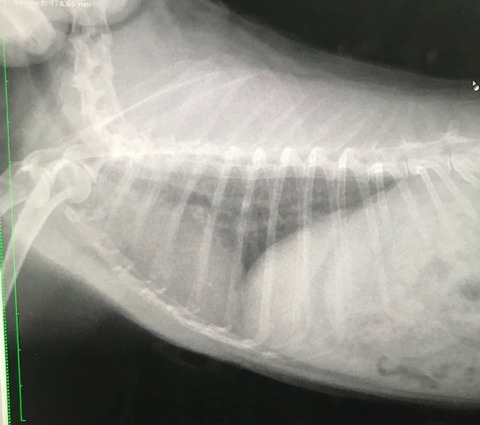

で、お歳、なこともあるのか呼吸の様子も少し気になってたので、

念のためのレントゲンをお願いしました。

胸、お腹、諸々特に問題視する箇所はありませんでした